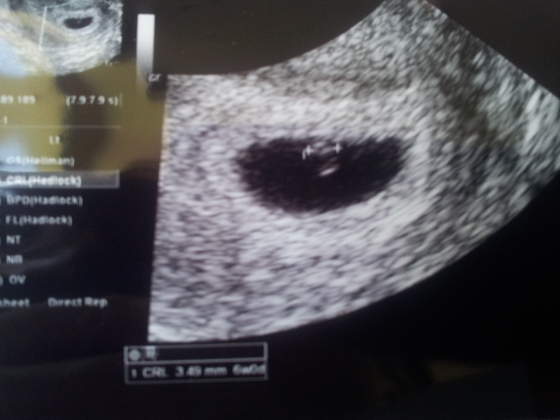

jest dzidzia 3,49 mm

serduszko bije w rytmie czaczanie slychac ale widac